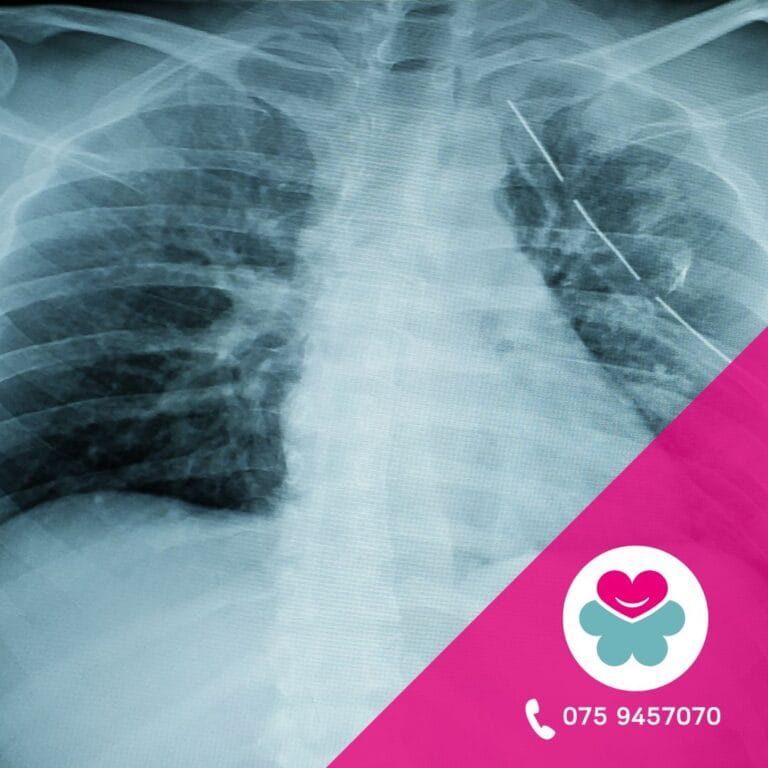

- Sottoporsi a una diagnosi per immagini (lastra o risonanza).